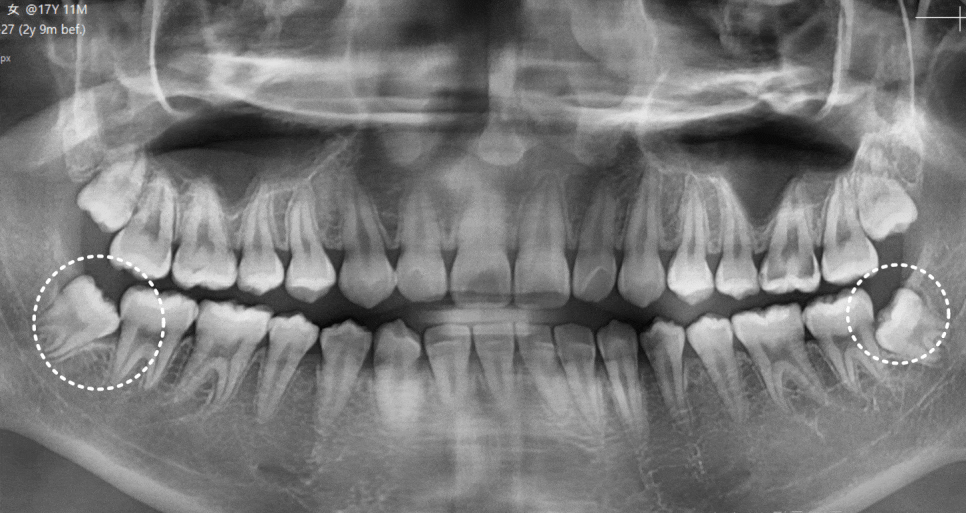

내원 당시 살펴보니

사랑니는 비스듬히 누워 반쯤만

잇몸 밖으로 나온 상태였습니다.

240919

문제는 사랑니 자체보다

바로 앞어금니 상태였습니다.

엑스레이와 입안 사진을 통해 확인해 보니,

230227(전) 240919 (후)

1년 반 사이에 사랑니뿐만 아니라,

앞에 치아까지 충치가 생겨있었습니다.

심지어 충치가 꽤나 많이 진행되어

이미 신경 가까이까지 진행된 상황이었습니다.